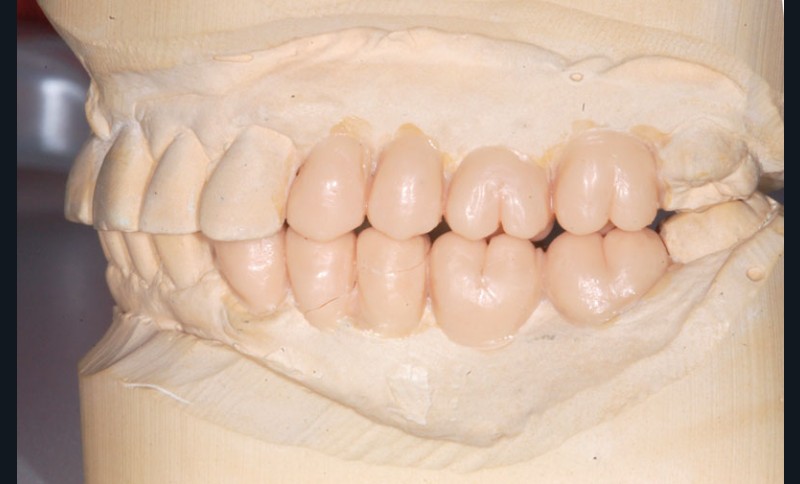

Après dépose du bridge mandibulaire et reprise du traitement endodontique, un bridge transitoire est réalisé à partir du wax-up. Une empreinte de celui-ci est faite avec Imprint™ 4 Preliminary Penta™ (3M ESPE).

L’automoulage est garni avec une résine composite (Protemp™ 4, 3M ESPE), avant ajustage et finition (roues spirales Sof-Lex™, 3M ESPE), pose du bridge transitoire.